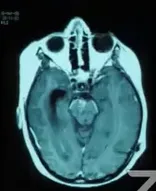

"从核磁共振的影像来看,孩子脑子里确实有一个肿瘤,长在中脑被盖——这是大脑深处最核心的区域,四周密布着控制眼球运动和肢体协调的神经核团。手术在技术上是可以做的,但风险也是客观存在的……"

术后病理结果随即出来:毛细胞星形细胞瘤,WHO 1级。这是胶质瘤家族里相对"温和"的类型,生长速度慢,扩散风险低。

复视(看东西出现重影)、行走不稳、头痛、恶心呕吐,这几组症状组合在一起,恰好构成了中脑被盖胶质瘤的典型临床表现。局灶性被盖部位的肿瘤,无论是手术入路的选择还是术后的长期管理,对神经外科医生来说都是一项巨大考验。这类病变大多数属于低级别胶质瘤,可以通过有框架或无框架立体定向活检的方式获取病理诊断。可供选择的手术入路包括经外侧裂入路、经颞叶入路以及经胼胝体入路,具体采用哪种方案,需结合肿瘤的体积以及其与软脑膜或脑室表面的位置关系综合判断。